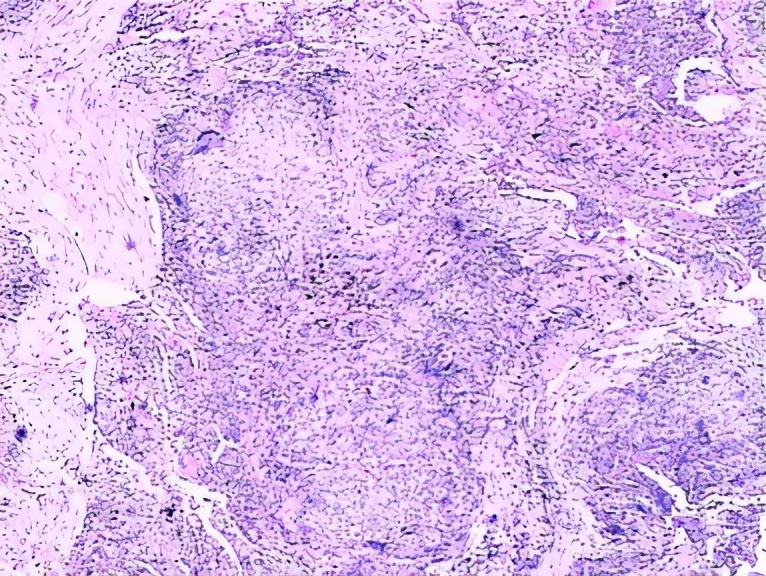

之后进行病理检查:肉芽肿,纤维化,细支气管炎,病理结果符合过敏性肺炎的表现,但是还没有问出病史。

ZYM:肉芽肿,NSIP-like,细支气管炎亚急性表现细胞性NSIP、细支气管炎和肉芽肿三联征,出现<75%。

CLX:慢性HP,纤维化比较明显,肺结构也被破坏,肉芽肿,UIP-lilke,细支气管炎。

慢性HP:气道中心性肺纤维化较明显。

下图都是肉芽肿性疾病,但是结节病的肉芽肿是边界非常清楚的间质性结节,过敏性肺炎的肉芽肿的边界比较模糊。

过敏性肺炎实际上是吸入抗原诱发的肺脏免疫炎性疾病,临床表现急、亚急性和慢性过程,以亚急性和慢性多见。目前倾向于按是否有纤维化进行分型,非纤维化型HP多指急性/亚急性,HRCT主要是小叶中心结节、斑片磨玻璃影、马赛克征。纤维化型多指慢性HP,HRCT还可见小叶间隔增厚,不规则粗、细网格,伴牵拉支扩,蜂窝等。病理特点为细支气管炎、不同类型不同程度的间质性肺炎(NSIP、OP、UIP)、肉芽肿。BALF:淋巴细胞增多,>40%。诊断主要是依据抗原及与疾病关系、HRCT、BAL-Lym↑。治疗为脱离抗原,酌情激素治疗。过敏性肺炎是一种可防可治的ILD,所以我们要提高认识,积极防诊治,改善病人生活质量。